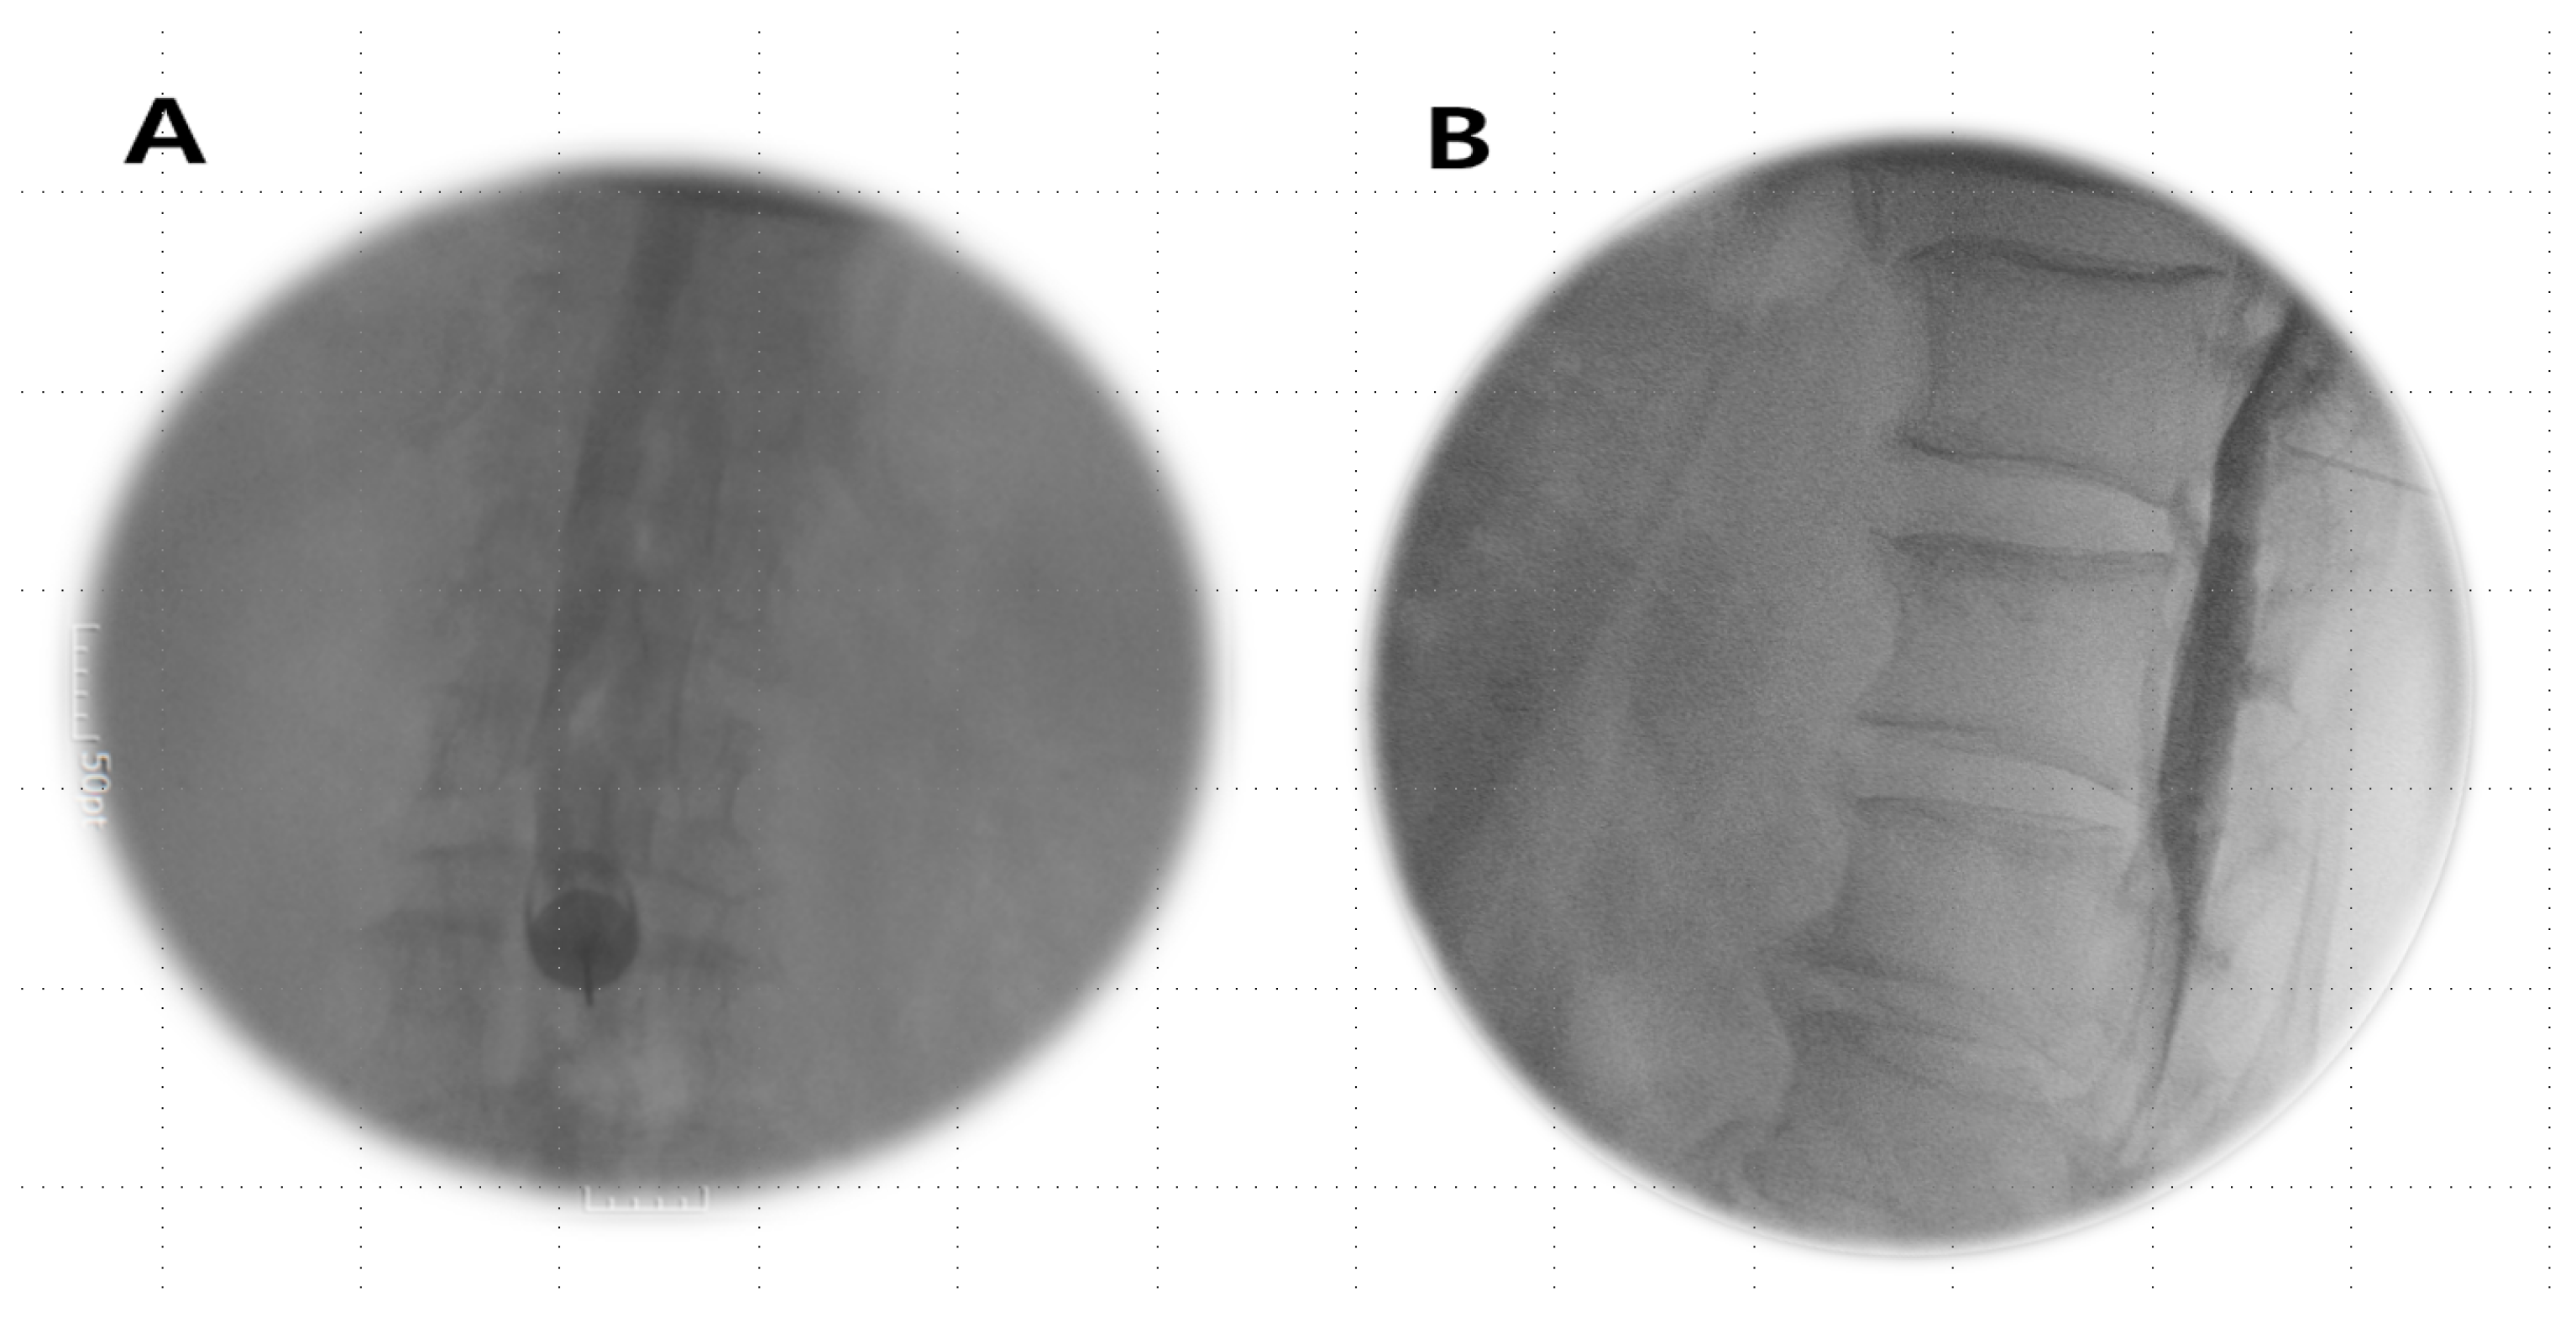

Anesthetics were administered if the Tuohy needle tip was situated within the epidural or subdural space (Figure 1A,B) or straddled between both spaces (Figure 2A,B).

Figure 1.

Subdural image. (A) AP view: a narrow column of contrast medium is confined to the central portion of the spinal canal and does not extend, outlining the exiting spinal nerve roots laterally. (B) Lateral view: the absence of CSF dilution and drainage; a longer duration persists, often remaining confined to the dorsal canal with a flat dorsal margin (dura mater) and an anterior bulging contrast (arachnoid mater) due to a smaller potential ventral subdural space.